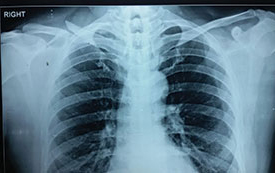

Case 5: Clavicle fracture

X-RAY 1

Displaced fracture right clavicle

Post operative x-ray

Case 6: Clavicle fracture

Displayed Clavicle fracture in a 24 years old cricketer

pre operative X-Ray showing displayed clavicle fracture

post operative x-ray showing fracture fixed with plate and screw